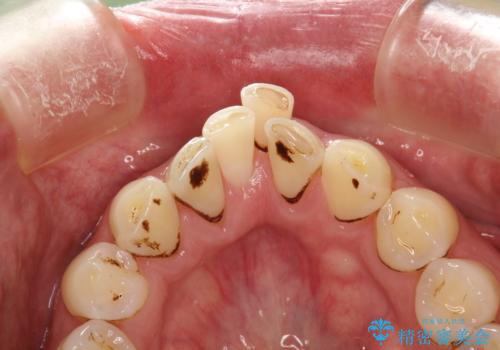

- 約3年ほど歯科医院での定期健診やクリーニングを受けてないとのことでした。全体的に歯石・着色などが付着していていたためPMTC60分コースを行いました。

分厚く歯石や着色が付着していると、汚れなのか虫歯なのかの判別がしづらい場合があります。しばらく定期健診やクリーニングを行っていない場合は、まずはしっかりと汚れを除去し、本来のご自身の歯の状態にすることで、より精密なお口の状態の診断が行えます。

CRは経年的に劣化や変色、着色が付着してしまうことがあります。

PMTCによって、CRと、ご自身の歯の境目の着色などがしっかりと落とせて目立たなくなる場合と、PMTCによってしっかりとクリーニングを行うと、CR自体が古く劣化・変色などしていて目立ってくる場合があります。気になる際は詰め替えを行います。